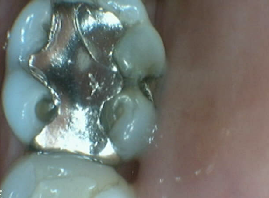

Bruxir Crown, Fractured Alloy